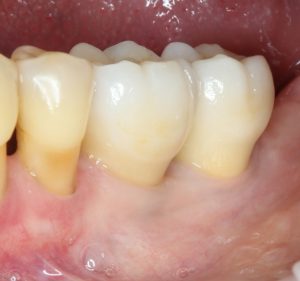

Но это еще не самое веселое. Допустим, мы решили проблему соединения «имплант-абатмент», у нас нет проблем с люфтами, а сам имплантат настолько хорошо интегрировался, что способен любую нагрузку в любом направлении. Возникает другая проблема — размер супраструктуры и соответствие ее нормальной биологической длине коронки зуба:

На фотографии выше, коронки опираются на обычные импланты, но даже в этом случае увеличение высоты супраструктуры усложняет гигиену и требует более пристального дальнейшего наблюдения. С ультракороткими имплантами, если честно, всё еще хуже.

Как будет выглядеть такая конструкция? Какой длины будут коронки? Возможно, на эстетику даже можно забить, ведь для некоторых людей красота зубов в боковом сегменте челюсти за пределами эстетически значимой зоны не так важна, но… как быть с уходом за протетической конструкцией и ежедневной гигиеной? Ведь, чем больше по размеру протез, тем сложнее за ним ухаживать. Тем больше мест, где может остаться зубной налет, а это, как вы понимаете, может привести к очень неприятным последствиям — периимплантиту, что для ультракоротких имплантов очень критично. А застревание пищи между протезом и десной? Можно ли назвать это «повышением качества жизни пациента»? Вряд ли.